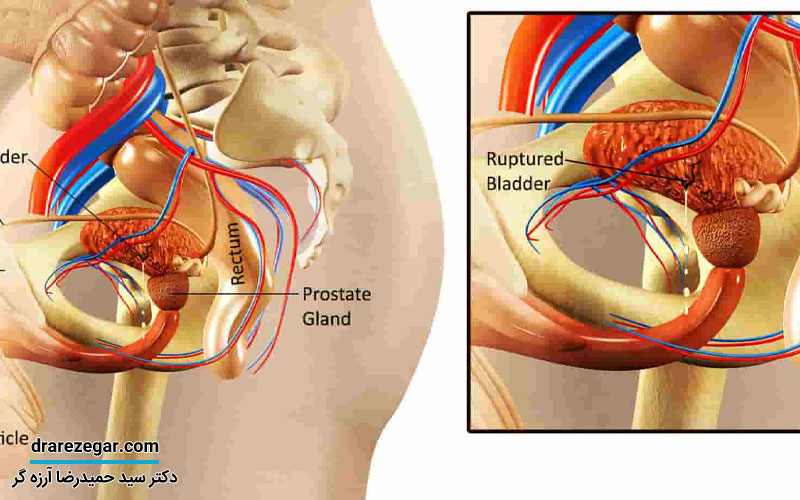

پارگی مثانه به چه شکل هایی اتفاق می افتد؟

نحوه پاره شدن مثانه ممکن است برای هر فرد با توجه علت آن متفاوت باشد. با توجه به بررسی های انجام شده، پاره شدن مثانه بر اساس اندازه پارگی و محل آن به چند دسته تقسیم می شوند که عبارت هستند از:

4. پارگی داخل صفاقی ( علت این نوع پارگی تحت فشار قرار گرفتن مثانه در حالت پر بودن است)

5. پارگی خارج صفاقی ( علت این نوع پارگی برخورد مستقیم استخوان بعد از شکستگی به شکم است)

6. پارگی ترکیبی ( پارگی بخش داخلی و خارجی صفاق به صورت همزمان)

طبق بررسی ها و نتایجی که در خصوص رابطه سن و پارگی مثانه وجود دارد؛ احتمال پاره شدن مثانه در سنین پایین و برای کودکان بیشتر از افراد بزرگسال است. در واقع مثانه در سنین کودکی به عنوان یکی از اندام های داخل شکم شناخته می شود.

بر این اساس ممکن است در اثر ضربه دچار شکستگی شوند. همچنین باید به این مسئله توجه شود که در سنین بالاتر و در افراد بزرگسال، به دلیل محافظت شدن مثانه توسط استخوان های لگن، احتمال پارگی آن در اثر ضربه یا شکستگی بسیار کمتر است.